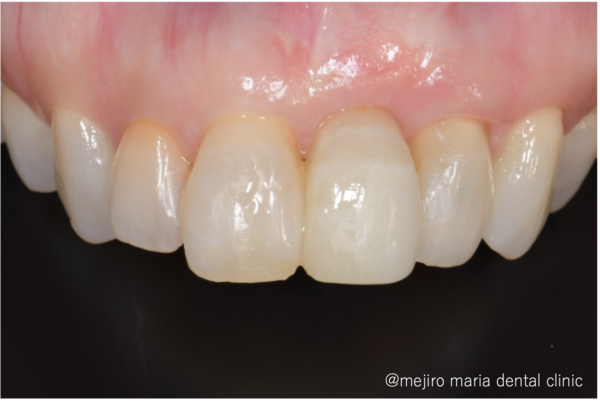

この症例では抜歯、歯槽堤保存術後4ヶ月ほど経ったところで補綴治療へと移行しました。

先述の「接着性ブリッジ」を選択しましたのでほとんど歯を削っていません。高い接着力を持つ材料を使い、隣の歯にセラミックの歯を貼り付けているのです。

歯槽堤保存術を行ったことでほとんど歯茎は凹むことなく、自然な見た目で治療を終えることができました。